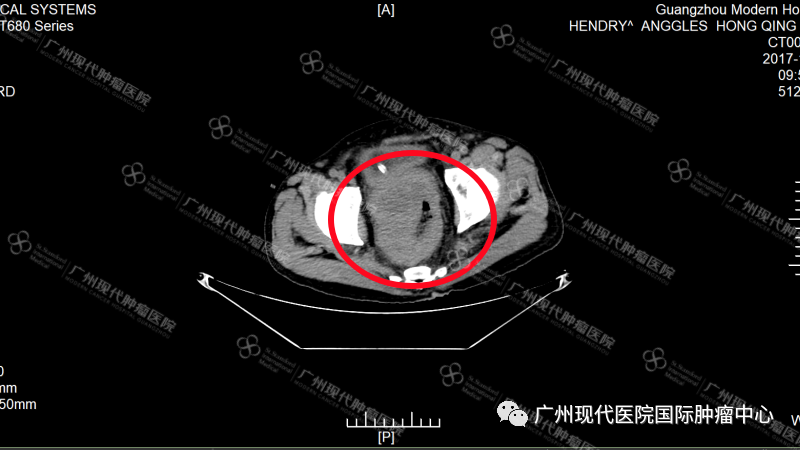

对此,洪清祥的孩子并未放弃寻求治疗的机会,最终通过网络检索了解到了圣丹福广州现代肿瘤医院拥有微创综合治疗技术可避免单一治疗方案所带来的风险。经过与家人们慎重考虑与商议,2017年11月,洪清祥在家人的陪伴下毅然决然地来到了我院。经详细检查发现,洪清祥直肠内存在大小约8*10 cm的肿瘤,并确诊为IV期直肠癌。

2017年至2020年间,洪清祥多次往返两国,一步步配合医院治疗控制病情,直到2020年最后一次CT检查,发现他直肠内的肿瘤已成功从10cm缩小至2cm,肿瘤得到了十分有效的控制。这缩小了的8cm,是微创治疗为洪清祥带来的曙光,更仿佛是上天对他不远万里跨国求医、以不抛弃不放弃的心态对抗癌症的褒奖。至此,洪清祥的跨国就医之旅正式告一段落。

2017年洪清祥来院初诊CT图